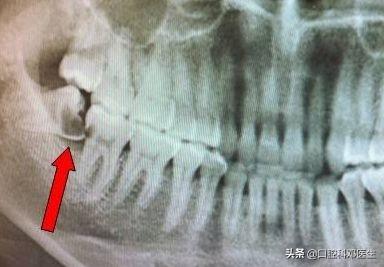

1.反复发炎的智齿

时不时的来个牙龈肿痛,吞咽痛,每次都要让你痛苦好几天,说明由于智齿的原因,导致牙龈容易发炎,拔掉智齿将是明智的选择!